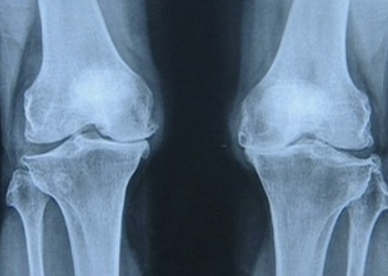

큰 어머니는 무릎이 안좋아서

10분 이상을 걷지 못한다고 하십니다.

얼굴에 근심이 가득한 어른의 얼굴을 보니

괜시리 제 마음도 안 좋아집니다.